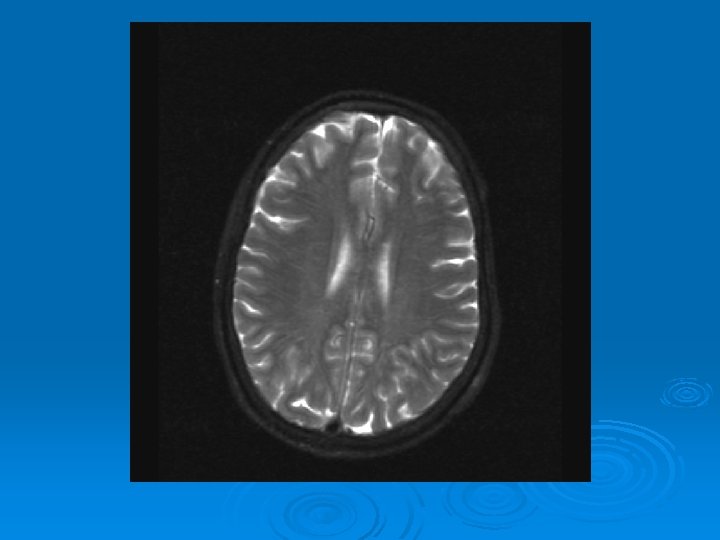

MRI: 2/9/2007 Ø 1. Leptomeningeal enhancement, most prominently seen over the posterior parietal and occipital lobes.

CMV: Ventriculoencephalitis Ø Clinical: Can have abrupt presentation of confusion, apathy, impaired memory, withdrawal, nystagmus, motor weakness, cranial nerve deficits, ataxia, seizures, coma. Can rapidly progress. Ø Labs: CSF: Monocytic Pleocytosis, Low Glucose CMV PCR Positive in CSF: (Sensitivity, Specifity 80, 90%, PPV, NPV, 86 -92, 9598%) Serum CMV viremia Ø Ø Ø MRI: Subependymal enhancement, diffuse hyperintense T 2 WI, ventriculomegaly.

MRI of CMV patient Magnetic resonance images of a patient with cytomegalovirus ventriculitis Ependymal enhancement after injection of gadolinium. DPTA seen on coronal T 1 -weighted image. Ø Highly abnormal ependmal signal on proton densityweighted image of the brain in axial section. Ø Ø See images in: l Arribas et al, Cytomegalovirus Encephalitis, Annals of Internal Medicine, 1996, Vol 125, Issue 7